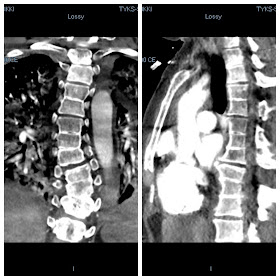

Rintarankaa edestä ja sivulta CT-kuvassa. Kaksi kolmoisblokkinikamaan, ja tavallinen blokkinikama. Ylhäällä kapeita nikamavälejä. Eikä tuo vinoutumakaan ihan normaalilta näytä. Rintarangan skolioosi.